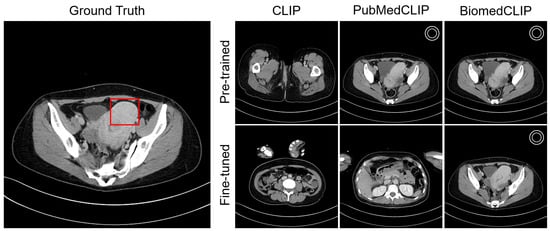

4.4. Visualization

Appendix C. Visualization

Appendix C.2. Organ Awareness